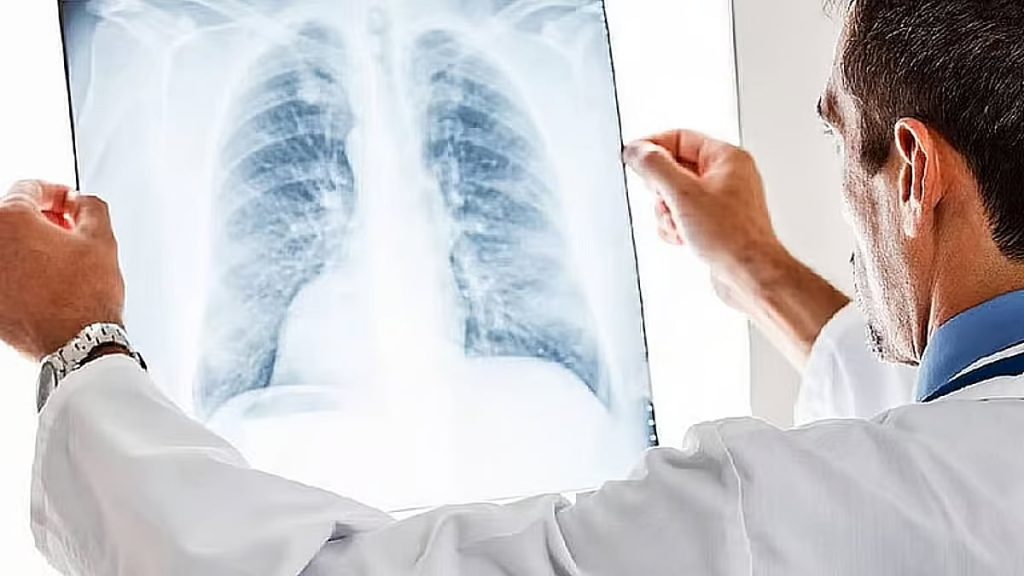

أوضحت مدينة الملك سعود الطبية الفرق بين الورم الحميد والورم السرطاني.

وقالت سعود الطبية في إنفوجراف توضيحي نشرته عبر حسابها الرسمي على منصة “إكس”: ” إن الورم الحميد يعد كتلة واحدة محددة في أغلب الحالات، ينمو ببطء ولا يمتلك القدرة على الانتشار داخل الجسم، وغالباً ما يكون محاطا بغشاء خارجي يحد من نموه، ولا يسبب عادة أعراضا خطيرة، كما أن احتمالية عودته بعد الاستئصال منخفضة، ولا يشكل خطرا مباشرا على حياة المريض”.

وتابعت:” أما الورم السرطاني فيكون غالبا على هيئة كتلة غير منتظمة وسريعة النمو، وقد تكون متفرعة وغير محاطة بغشاء خارجي، مما يزيد من احتمالية انتشار الخلايا إلى أعضاء أخرى في الجسم، كما أن هذا النوع قد يعود بعد الاستئصال ويعد من الأورام التي قد تسبب الوفاة إذا لم تكتشف وتعالج مبكرا”.

️| ما الفرق بين الورم الحميد والسرطاني؟

التمييز بينهما يساعد على فهم الحالة وتحديد الطريقة الأمثل للعلاج، ويُعد الاكتشاف المبكر العامل الأهم في تحسين النتائج.#10KSA pic.twitter.com/JQVXsMdcm1— مدينة الملك سعود الطبية (@ksmcmedia) December 9, 2025